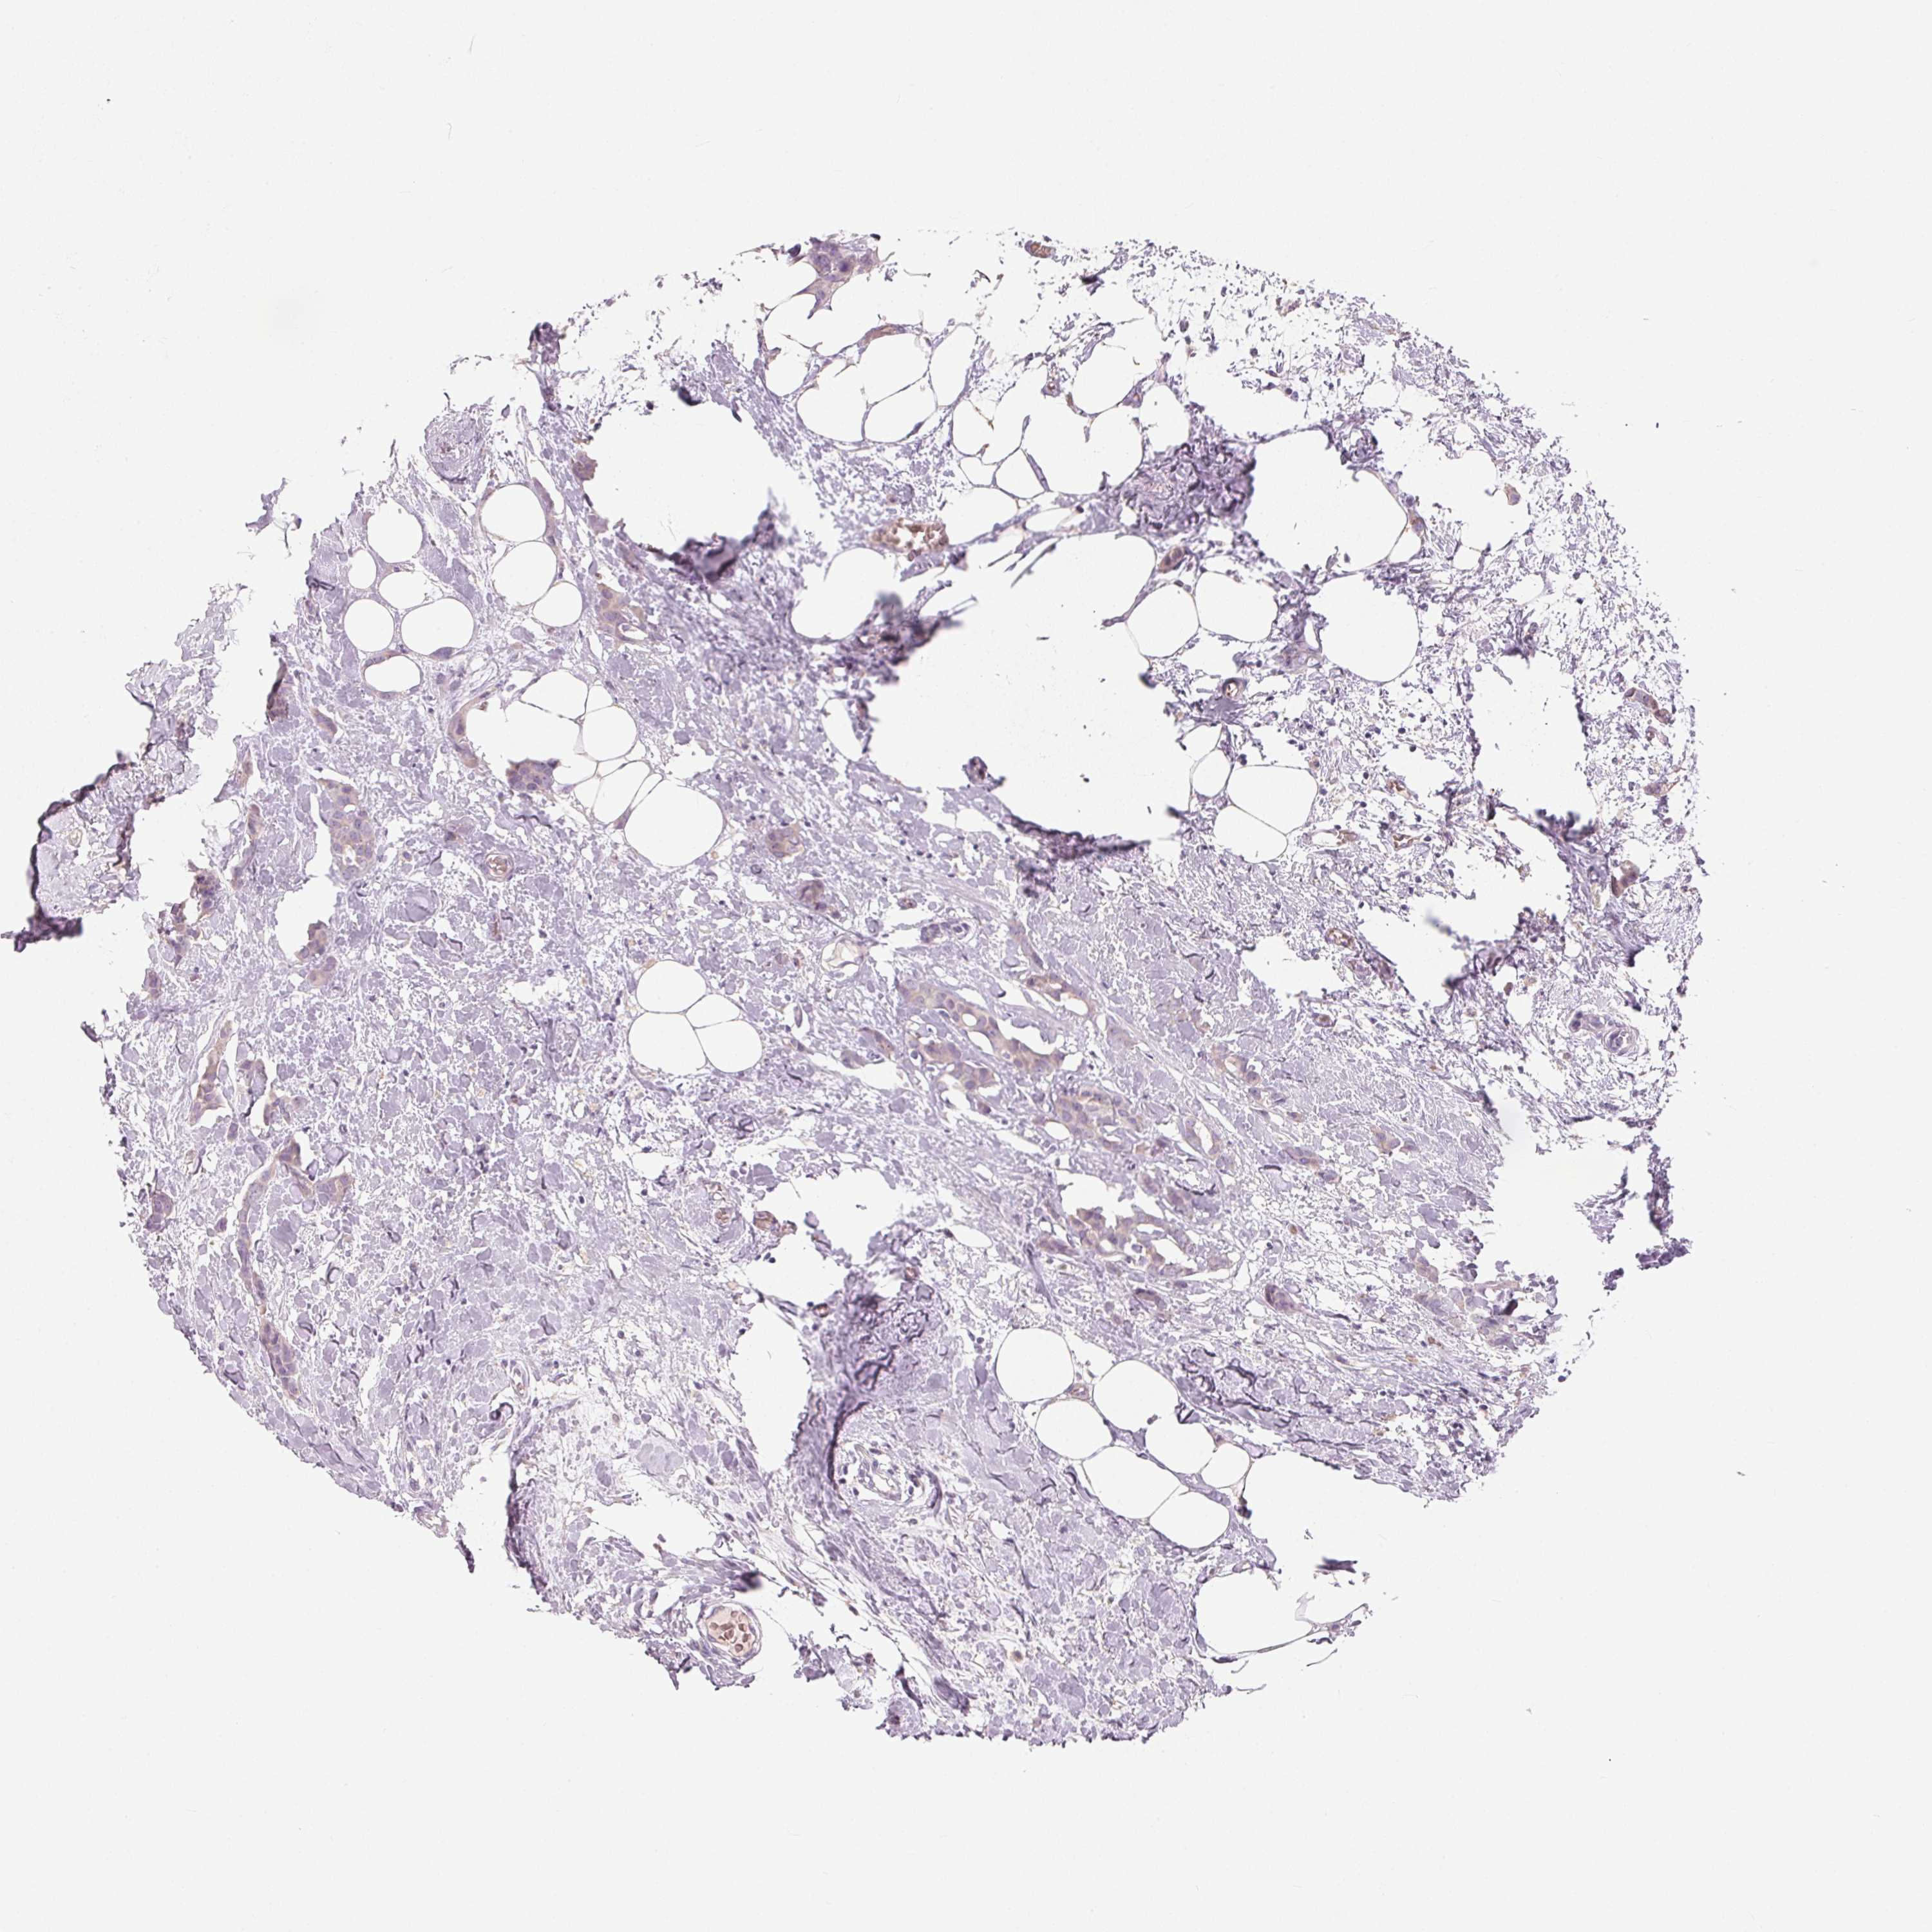

CANCER BREAST CANCER Show tissue menu

BRCA TCGA BRCA VALIDATION PROTEIN EXPRESSION